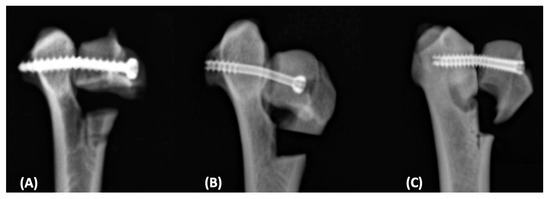

2.2.1. 3.0 mm Cortical Screw with Lag Fashion (Group 1)

2.2.2. 3.0 mm Partially Threaded Cannulated Screw (Group 2)

2.2.3. 3.5 mm Fully Threaded Cannulated Headless Screw (Group 3)